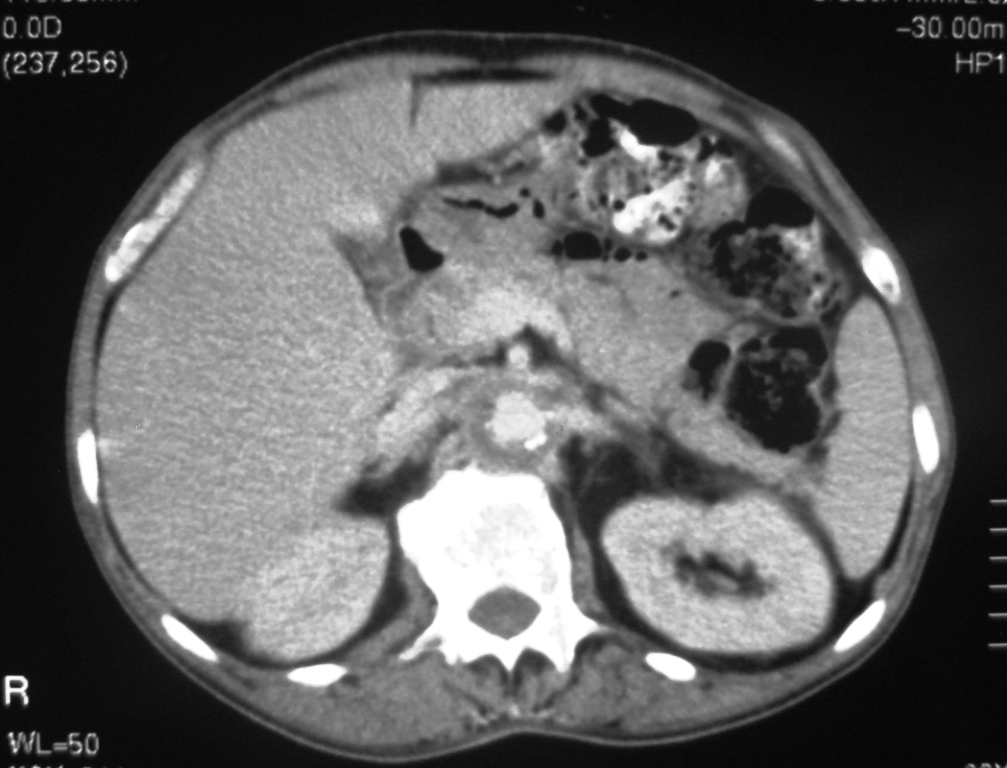

We describe the case of a 60-year-old diabetic man who was admitted to our hospital with keto-acidosis and rapidly developed sepsis and a mycotic abdominal aortic aneurysm (AAA) with branch involvement. Early and late findings on serial computed tomography (CT) examinations are presented. Awareness and recognition of early imaging findings associated with infectious aortitis and serial CT examination in cases of patients with sepsis and predisposing factors are essential for prompt diagnosis and treatment.